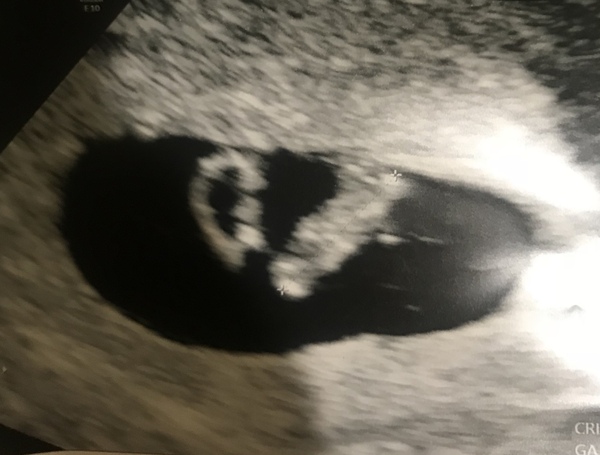

brighteye3986 · 22/03/2019 05:03

I've not been on much but wanted to update... I had my scan yesterday at 7+3 and everything is going well. Baby's heart was flickering fast on the screen and everything is where it should be. I'm so happy.

Unsureursula · 22/03/2019 09:45

Hello all! Just on way back from scan dated at 6wks 6days. All looks good and little heart was flicking away on the screen! Feel much better but obviously still a long way to go so trying not to get too excited!